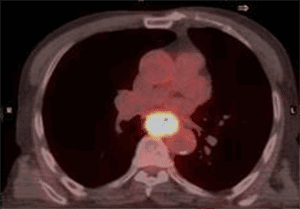

Advancing your expertise in PET-CT imaging to enhance cancer diagnosis and improve patient care.

Since its establishment in 2017, the Christie PET-CT Academy has been a leading centre of excellence for advancing education and training of professionals across the full spectrum of PET-CT diagnostic services. Part of The Christie NHS Foundation Trust the PET-CT Academy operates in partnership with Alliance Medical as part of the National Contract 1 (NC1) Molecular Imaging Collaborative Network (MICN), to provide a skilled workforce to meet ever-increasing patient needs across England, by equipping professionals to enhance diagnostic capabilities and work toward closing the gap in cancer survivorship.